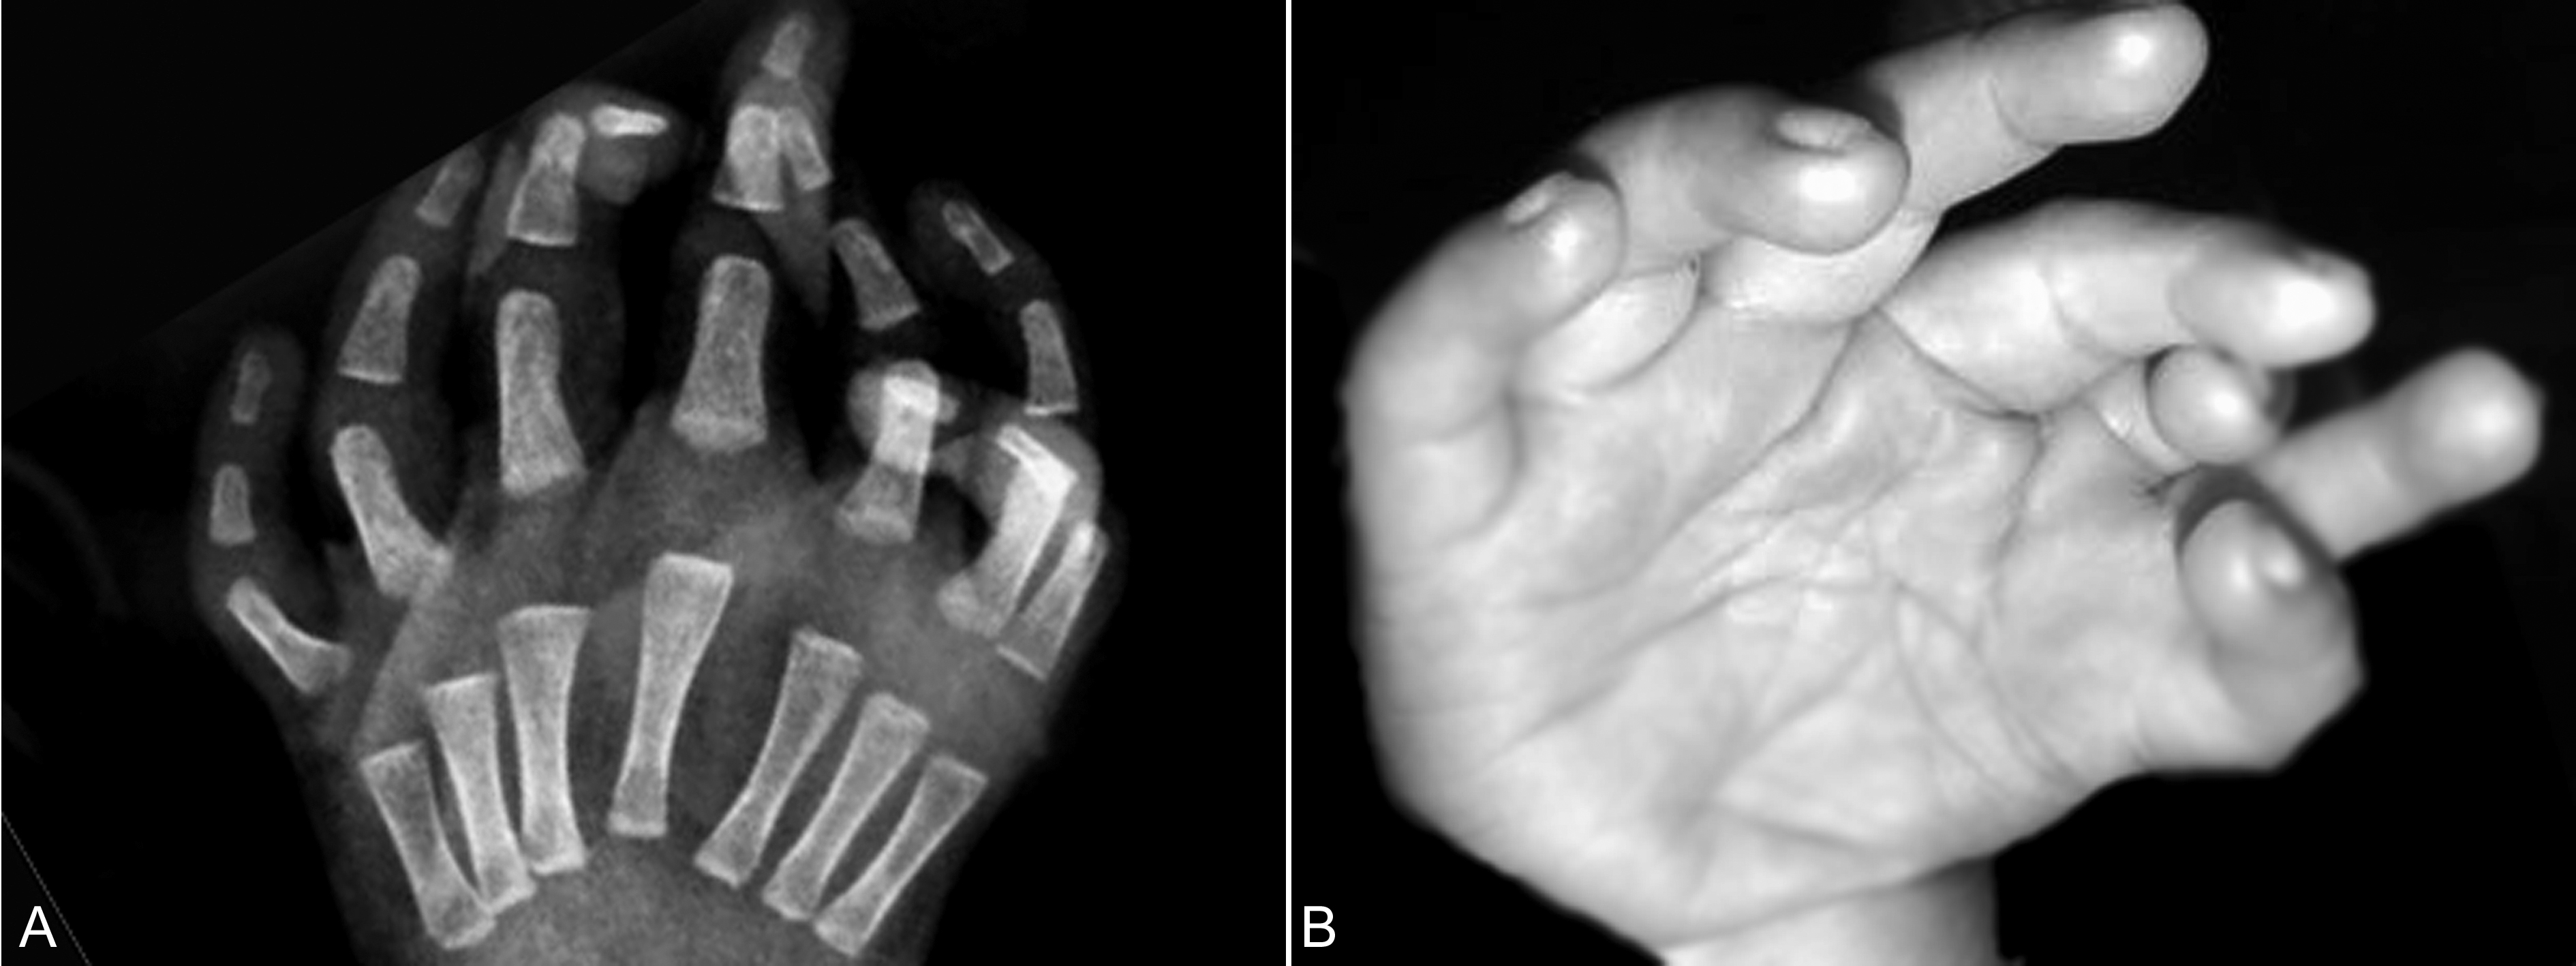

4.尺骨重复 尺骨重复又称尺侧复肢畸形或镜手畸形,是非常罕见的上肢畸形,典型的变化是前臂有两根尺骨形成,挠骨及拇指缺失,沿轴线对称性或非对称性6指~8指多指畸形(图6)。多数两根尺骨均发育异常,腕骨重复排列。超声显像检查显示手部对称性多指,拇指缺失,上臂显示基本一致的两根长骨;有时上臂仅有一根长骨,但显示拇指缺失并对称性多指时仍可诊断镜手畸形。

图6镜手畸形X检查(A)及手部图像(B)